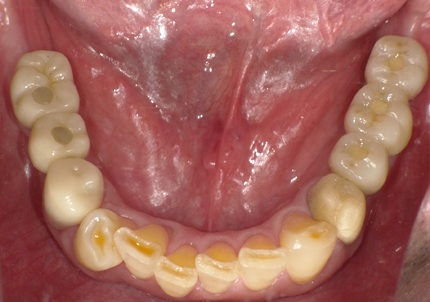

1.初診時口腔内写真(2014年6月)